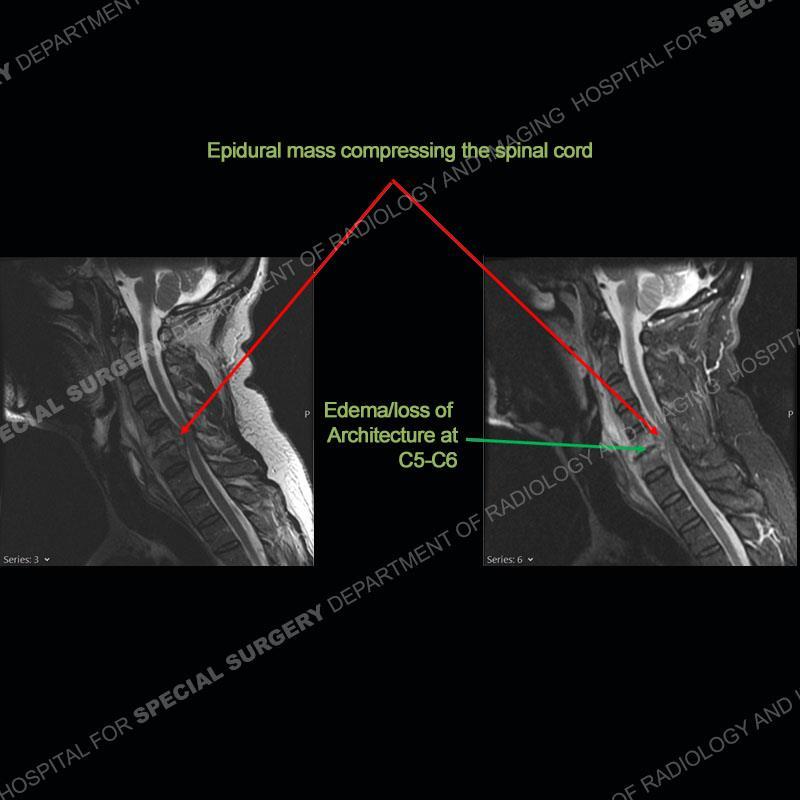

The radiographs demonstrate a prevertebral soft tissue fullness centered at C5-C6 that persists even on extension. There is a slight loss of disc height at C5-C6. The CT more readily shows the prevertebral soft tissue swelling at C5C6 where there is a punctate focus of gas. On the MRI, there is a marked amount of edema and a heterogeneous collection in the prevertebral soft tissue at C5-C6. Edema is present of the C5 and C6 vertebral bodies with a loss of the normal architecture about the disc space. A heterogeneous epidural collection has formed that causes compression of the spinal cord asymmetric to the left side and also precipitates severe left sided neural foraminal stenosis.